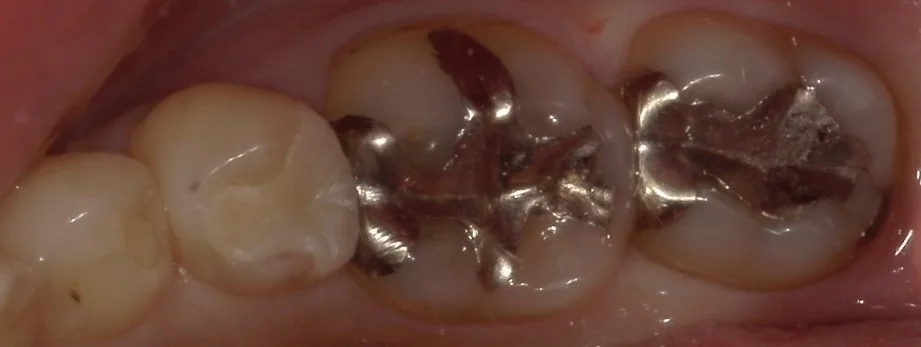

まずは術前です。

今回行ったのは、画面上で右側3つの歯です。

奥二つの金属の詰め物の下に虫歯があったのと・・・

3~4カ月ほど前に他院にて治療されたセラミックInの適合が悪かったためです。